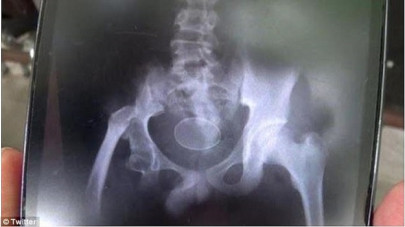

Teenage boy claims to have laid 20 eggs in two years

Doctors are puzzled by his condition, saying its 'impossible' for eggs to form inside the human body